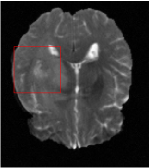

All the experiments are implemented on a Windows workstation with Intel Core i9 CPU at 3.3GHz and an Nvidia GTX-1080Ti GPU with 11GB of graphics card memory via TensorFlow Abadi et al. (2016). The parameters in the proposed network are initialized by using Xavier initialization Glorot and Bengio (2010). We trained the meta-learning network with four tasks synergistically associated with four different CS ratios: 10%, 20%, 30%, and 40%, and test the well-trained model on the testing dataset with the same masks of these four ratios. We have 300 training data for each CS ratio, which amount to total of 1200 images in the training dataset. The results for and MR reconstructions are shown in Tables 5.4 and 5.4 respectively. The associated reconstructed images are displayed in Figures 1 and 3. We also test the well-trained meta-learning model on unseen tasks with radio masks for skewed ratios: 15%, 25%, 35%, and random Cartesian masks with ratios 10%, 20%, 30% and 40%. The task-specific parameter for the unseen tasks are retrained for different masks with different sampling ratios individually with fixed task-invariant parameters . In this experiments, we only need to learn for three skewed CS ratios with radio mask and four regular CS ratios with Cartesian masks. The experimental training proceed on less data and iterations, where we performed on 100 MR images with 50 epochs. For example, for reconstructing MR images with CS ratio 15% radio mask, we fix the parameter and retrain the task-specific parameter on 100 raw data with 50 epochs, then test with renewed on our testing data set with raw measurement that sampled from radio mask with CS ratio 15%. The results associated with radio masks are shown in Table 5.4 and 5.4, Figure 2 and 4 for and images respectively. The results associated with Cartesian masks are list in Table 5.4 and reconstructed images are displayed in Figure 5.

Qualitative comparison between conventional and Meta-learning methods are shown in Figure 1 and 3, which display the reconstructed MR images of the same slice for T1 and T2 respectively, we label the zoomed-in details of HGG in the red boxes. We observe the evidence that conventional learning is more blurry and lost sharp edges, especially in lower CS ratios. From the point-wise error map, we find meta-learning has the ability to reduce noises especially in some detailed and complicated regions comparing to conventional learning.

In this section, we test the generalizability of the proposed model that tests on unseen tasks. We fix the well-trained task-invariant parameter and only train for sampling ratios 15%, 25% and 35% with radio masks and sampling ratios 10%, 20%, 30% and 40% with Cartesian masks. In this experiment, we only used 100 training data for each CS ratio and apply a total of 50 epochs. The averaged evaluation values and standard deviations are listed in Table 5.4 and 5.4 for reconstructed T1 and T2 brain images respectively that proceed with radio masks, and Table 5.4 shows the qualitative performance for reconstructed T2 brain image that applied random Cartesian sampling masks. In T1 image reconstruction results, meta-learning improved 1.6921 dB in PSNR for 15% CS ratio, 1.6608 dB for 25% CS ratio, and 0.5764 dB for 35% comparing to the conventional method, which in the tendency that the level of reconstruction quality for lower CS ratios improved more than higher CS ratios. A similar trend happens in T2 reconstruction results with different sampling masks. The qualitative comparisons are illustrated in Figure 2, 4 and 5 for T1 and T2 images tested in skewed CS ratios in radio masks, and T2 images tested in Cartesian masks with regular CS ratios respectively. In the experiments that conducted with radio masks, meta-learning is superior to conventional learning especially at CS ratio 15%, one can observe that the detailed region in red boxes keeps edges and is more close to the true image, while conventional method reconstructions are hazier and lost details in some complicated tissue. The point-wise error map also indicates that Meta-learning has the ability to suppress noises.